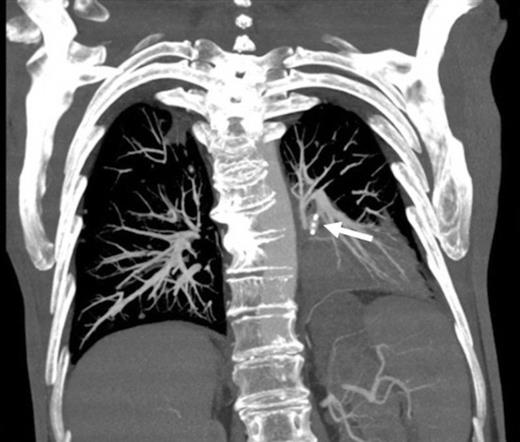

Coronal reconstruction of CTPA taken 2 days after embolisation demonstrating successful ongoing exclusion of the PA aneurysm. Note the AVP (arrow) and continued filling of unaffected lower lobe segmental pulmonary arterial branches

Digital subtraction angiography post deployment of the AVP 4 device in the PA branch feeding the aneurysm (arrow). No residual or collateral filling seen